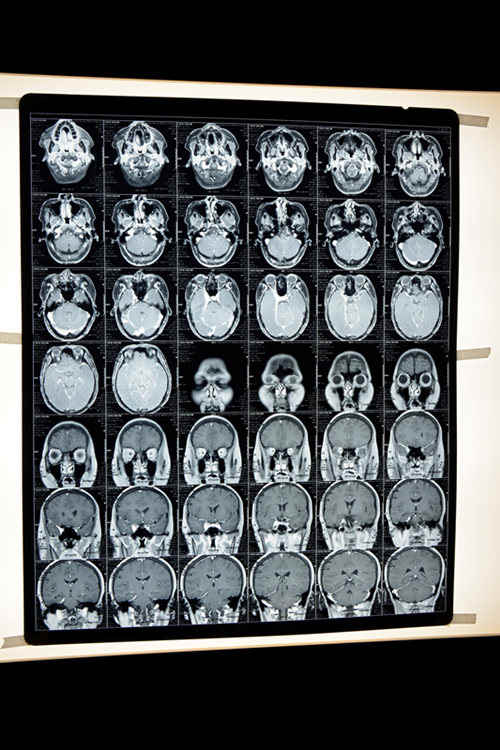

患者入院時的磁共振(MRI)影像顯示:腦血管嚴重堵塞

余主任說,患者的血粘度太高,血液呈高凝狀態(tài),使腦血管靜脈通道堵塞形成血栓,引發(fā)頭痛,血栓還堵塞了視神經(jīng),造成失明。這種疾病在急性期采用西醫(yī)療法,慢性期采用中醫(yī)療法,需要靈活運用中西醫(yī)結(jié)合治療才能取得理想的治療效果。